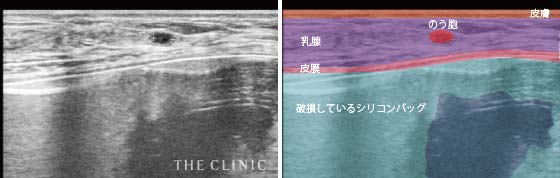

乳腺や脂肪、筋肉などの層の状態をみることができるので、シリコンバッグのまわりにある皮膜の厚さや石灰化の状態だけではなく、シリコンバッグが挿入されている正確な位置やシリコンバッグの破損なども確認することができます。

- シリコンバッグ破損(皮膜内破裂)+のう胞

- バッグが破損しているため形が不均一に